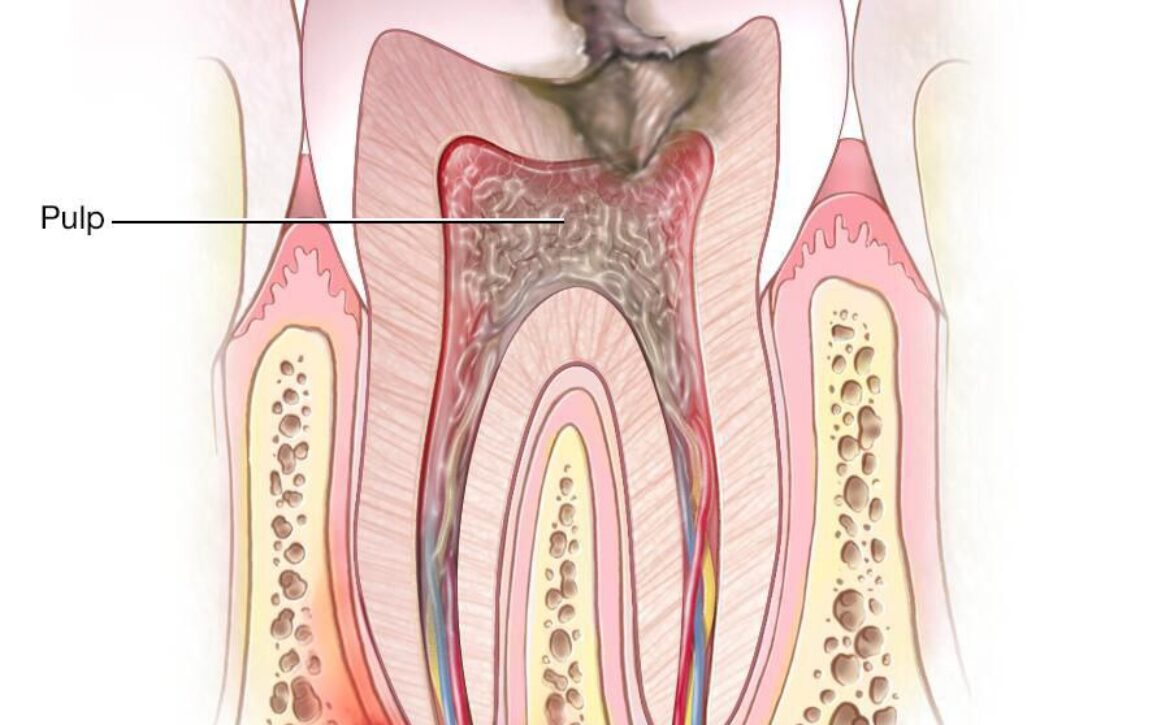

ارتباط عفونت دندان با التهاب بدن

عفونتهای درماننشده دندانی میتوانند باعث ورود باکتریها به جریان خون شوند. این مسئله ممکن است سطح التهاب عمومی بدن را افزایش دهد؛ عاملی که با بیماریهای قلبی–عروقی، دیابت و اختلالات متابولیک در ارتباط است.

درمان بهموقع عفونت ریشه دندان فقط برای جلوگیری از درد یا از دست رفتن دندان نیست؛ بلکه میتواند نقش مهمی در کاهش التهاب مزمن بدن داشته باشد. از آنجا که التهاب مزمن یکی از عوامل خطر بیماریهای قلبی محسوب میشود، حفظ سلامت دهان و دندان بخشی از مراقبت از سلامت عمومی بدن است.